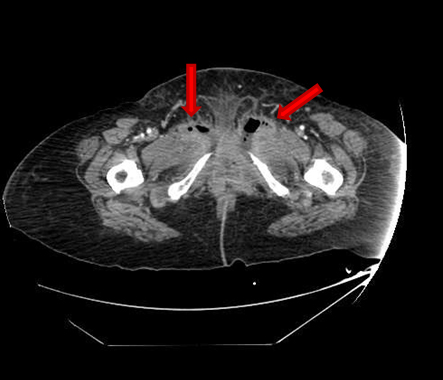

She presented on Emergency room suffering from fever, pelvic pain, and functional impairment of her right lower limb. Physical examination revealed bad smell vaginal flow and loss of strength on her right lower limb. Contrast computerized tomography and magnetic resonance images showed pelvic muscles impairment (Figure 1), inflamed bladder (Figure 2), and pelvic abscess lying from right psoas muscle to pubis bone, which presented radiologic signs of osteomyelitis (Figure 3) and (Figure 4).

Figure 2: CT scan image. Mild and diffuse thickening of bladder walls, with fat trabeculation. These signs suggest cystitis. Loss of fat distinction planes between bladder and rectum and vagina, probably related to previous radiotherapy.